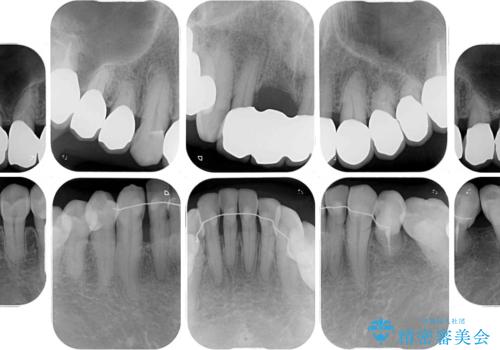

- 上の前歯が痛むとのことで来院された患者様です。

検査を行ったところ、前歯1本は周辺の骨が失われており、抜歯が必要でした。

上顎の奥歯は全体的に歯周ポケットが散見され出血が認められたため、歯周外科処置を行うこととしました。